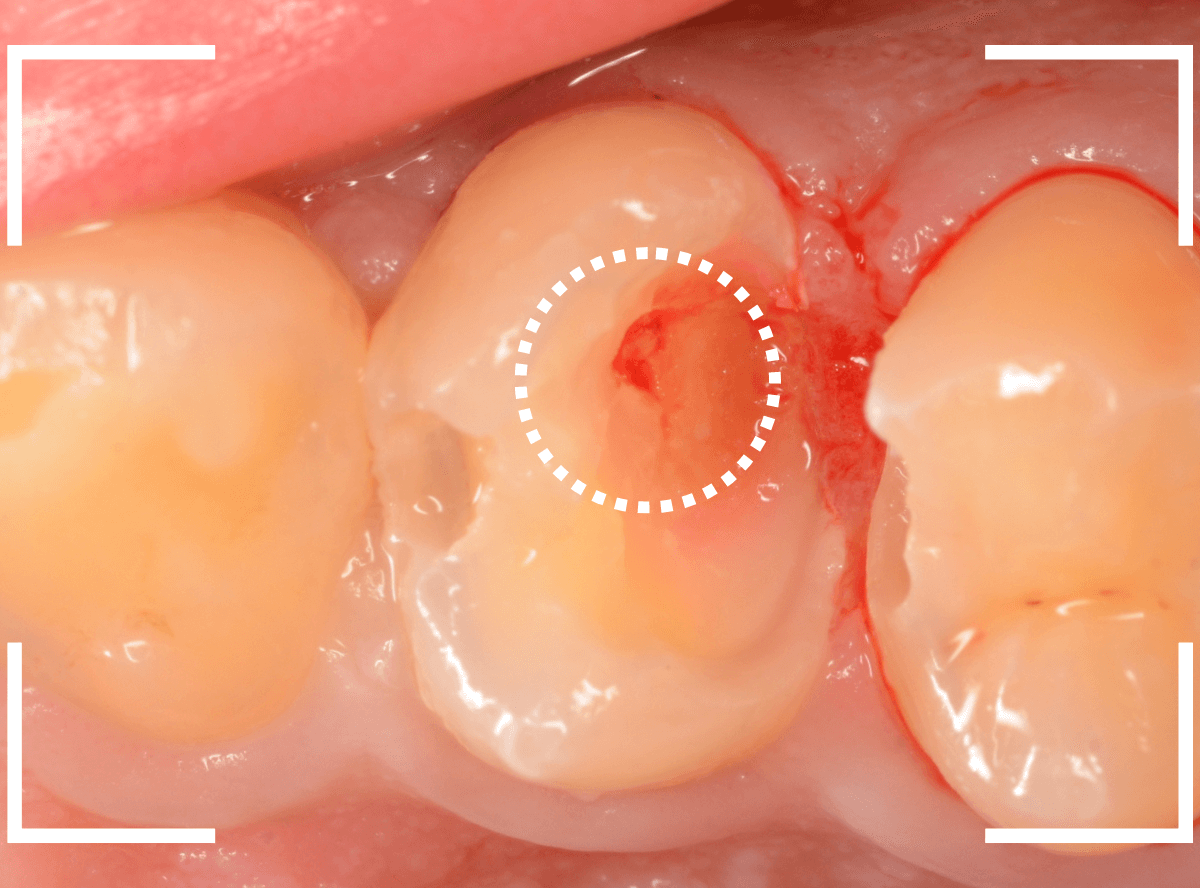

Case.22 痛みはないけど、歯のすきまから大きな虫歯

上の小臼歯の間が虫歯になっていた患者さんです。

症状はありませんし、見た目からも虫歯があるかはわかりませんでした。

治療を開始します。

少し削ると、中からすぐに虫歯が出てきました。

ある程度、虫歯を除去したところで、う蝕検知液で確認します。

赤く染まっている部分が虫歯です。

まだまだ虫歯が中で残っている状況で、かなり深い虫歯なのが確認できます。

全ての虫歯を除去しました。

レントゲン写真からある程度確認出来ましたが、歯の神経スレスレまで虫歯が進行していました。

ここまで虫歯が進行していても、全く症状を感じない事も多いです。